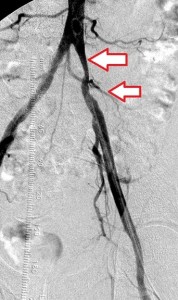

The images below illustrate percutaneous stenting of stenosis of the distal proximal and the mid left common iliac artery, without disease of the left external iliac artery in one of my patients who presented with left calf claudication. CTA of his abdominal aorta and arterial duplex ultrasound of his lower limbs ( images not shown) revealed left iliac stenosis, confirmed by the digital subtraction angiographic images in the first row. He did well following stenting of the diseased artery. Iliac arterial stenting stays open for nearly as long as surgical revascularization and at much less the morbidity and cost of the latter.